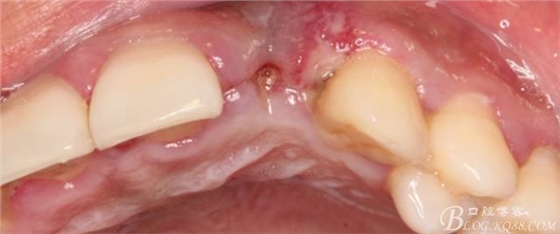

于是我果斷告知患者,手術(shù)失敗了,不能拖延,如不及時(shí)處理,炎癥繼續(xù)發(fā)展會(huì)很快波及鄰牙牙槽骨?;颊呓邮芪业慕ㄗh。切開(kāi)翻瓣,骨粉及生物膜消失了,骨吸收嚴(yán)重,幸運(yùn)的是,因?yàn)樘幚砑皶r(shí),鄰牙骨支持依然存在。